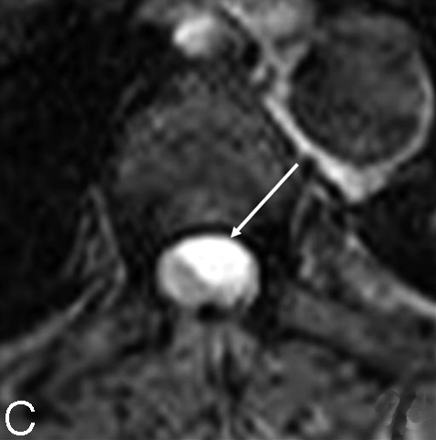

Three months after this second operation a control MR imaging (Fig 7) demonstrated, at the site of prior surgery, a recurrent cystic lesion behaving in a manner similar to that observed on the previous studies and also a new intradural extramedullary lesion at the level of L5. A homogeneous nodule was found with a slightly hyperintense aspect on T2-weighted-images (Fig 7A) enhancing strongly after contrast administration (Fig 7B). This new lesion was considered to be a drop metastasis, and surgery again confirmed an ependymoma grade II, though the behavior of the tumor was clinically aggressive.

Control MR imaging examination. Sagittal T2 (A) and T1-weighted gadolinium-enhanced (B) images disclosing an intradural L5 drop metastasis (confirmed by subsequent surgery). Moreover, at the site of prior surgery, the cord looks again newly deformed by a recurrent cystic lesion behaving in a similar way observed on the previous studies. This aspect is confirmed on the axial T2WI obtained at the T7 level (C): the cyst is left anterolaterally located (arrow).